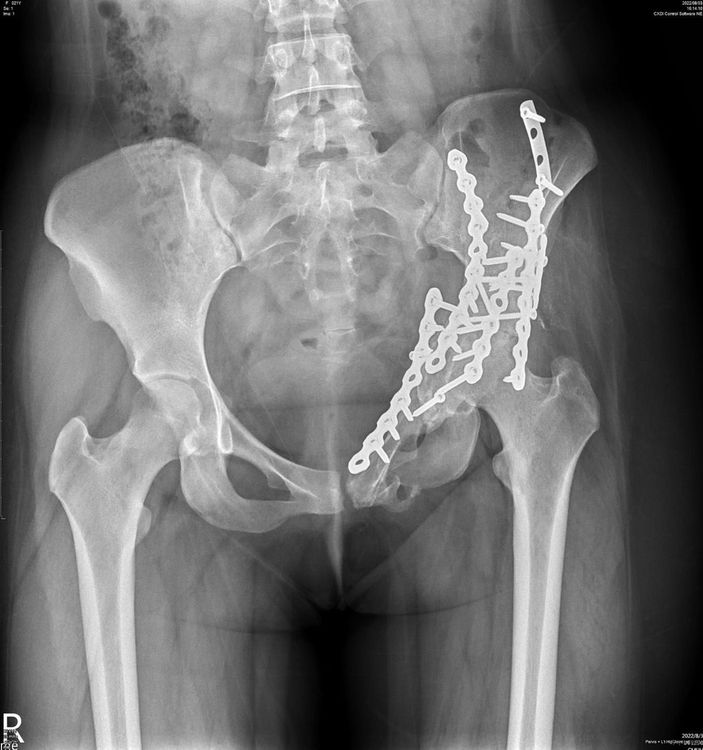

女大生的左側骨盆粉碎性骨折接受骨折復位固定手術,X光片呈現的是密密麻麻的鋼板和鋼釘。左側的股骨頭有創傷後骨壞死的情況發生。大里仁愛醫院提供

因為之前車禍造成的骨盆粉碎性骨折,X光片呈現的是密密麻麻的鋼板和鋼釘,左側的股骨頭還有創傷後骨壞死。在安排微創人工髖關節置換手術後,女大生兩隻腳不只一樣長、而且還有了活動自如又不痛的髖關節。手術當天就下床活動,開心的在病房走來走去,也終於可以好好睡個覺。